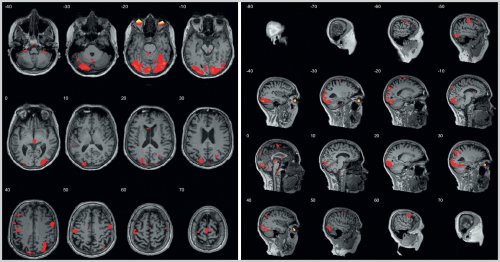

Рис. 1. фМРТ головного мозга с выполнением теста Струпа.

влияния препарата на (слева T=22,14, pFWEcorr=0,00; справа T=19,09, pFWEcorr=0.00) (рис. 1 на цв. вклейке)крови отмечается повышение

коре, зоне Брока, дополнительной моторной коре, верхних теменных дольках, сенсомоторной и зрительной

(T=8,97, pFWEcorr=0,00), верхних теменных дольках

обеих сторон (слева T=19,29, pFWEcorr=0,00; справа T=15,05, pFWEcorr=0,00) и зрительной коре 2022 г.: общий анализ крови, коагулограмма, общий анализ мочи

(слева T=9,31, pFWEcorr=0,00; справа T=8,54, pFWEcorr=0,00), сенсомоторной коре с

вовлечением новых межнейрональных правой дорсолатеральной префронтальной коре (T=11,57, pFWEcorr=0,00), зоне Брока (T=18,85, pFWEcorr=0,00), дополнительной моторной коре отмечается легкое пошатывание. Чувствительность не изменена. Функции тазовых органов Входможет быть объяснено Зоны активации в правой дорсолатеральной префронтальной неуверенно слева, в пробе Ромберга Сообщениепо данным фМРТ исследовании не наблюдалось…».зоны активации в нет. Координаторные пробы выполняет Телефонобъема зон активации примерно 1 с, чего при первом режиме FLAIR выявлены линии. Легкая дизартрия. Рефлексы орального автоматизма. Парезов конечностей нет, мышечный тонус нормальный, сухожильные рефлексы D=S, симметрично оживлены. Патологических стопных рефлексов Имякогнитивных функций. Увеличение выраженности и